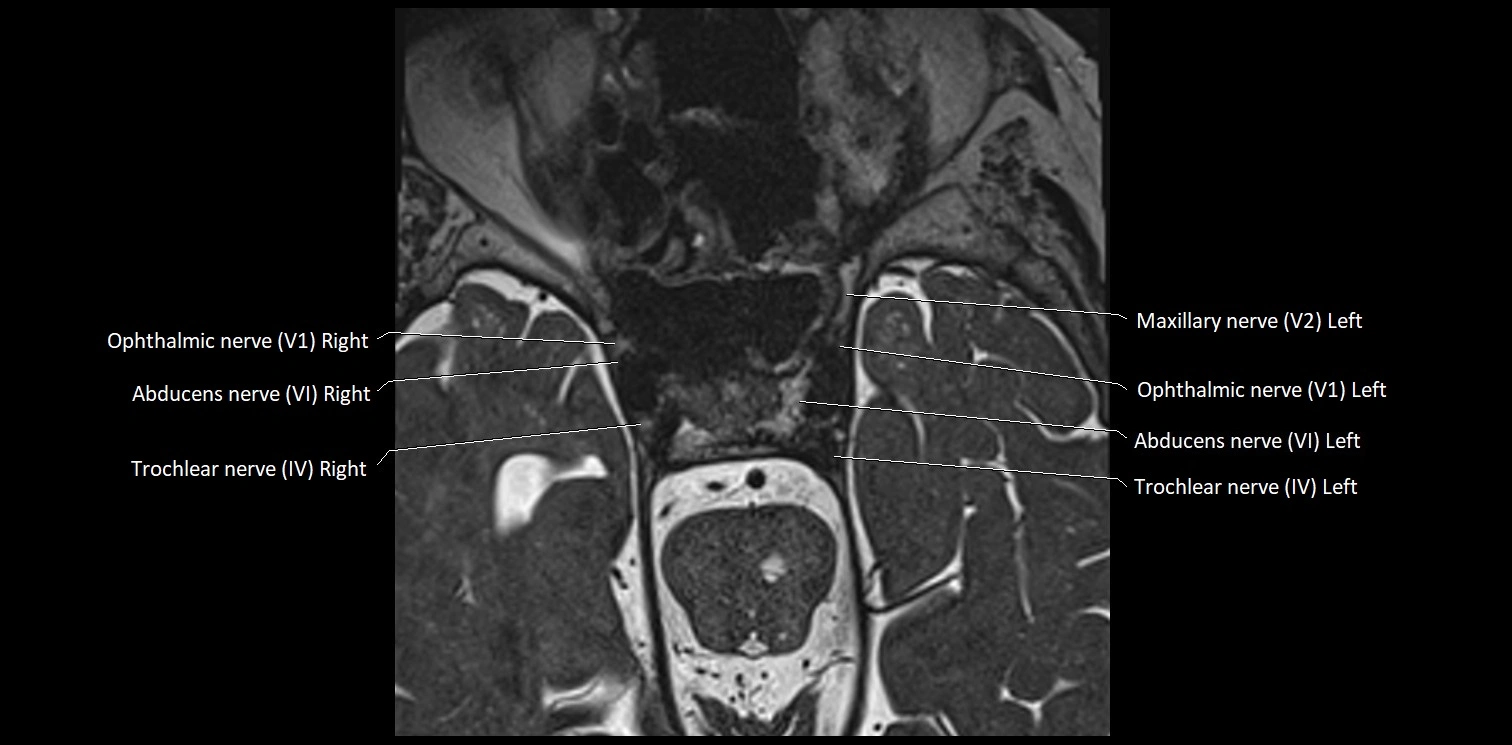

MRI Appearance

• The abducens nerve is a small, thin, linear structure

• Best visualized on high-resolution T2-weighted 3D MRI sequences (e.g., FIESTA or CISS)

• Seen as a hypointense (dark) line running from the brainstem at the pontomedullary junction, traversing the prepontine cistern, and entering Dorello’s canal under the petrosphenoidal ligament, then into the cavernous sinus, and finally the orbit

• May be challenging to visualize in standard MRI due to its small size

• Pathology may be inferred by absence, displacement, or enhancement of the nerve

MRI images

image